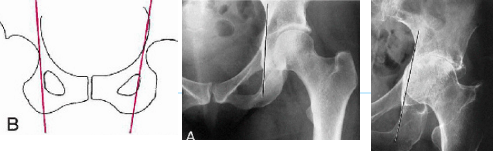

Q what is the name of this measurement? and what is the average + range?

A: Skinner's Line

assesses the position of the femoral head relative to the greater trochanter.

Normal Finding: The fovea capitis should lie at or above the trochanteric line.